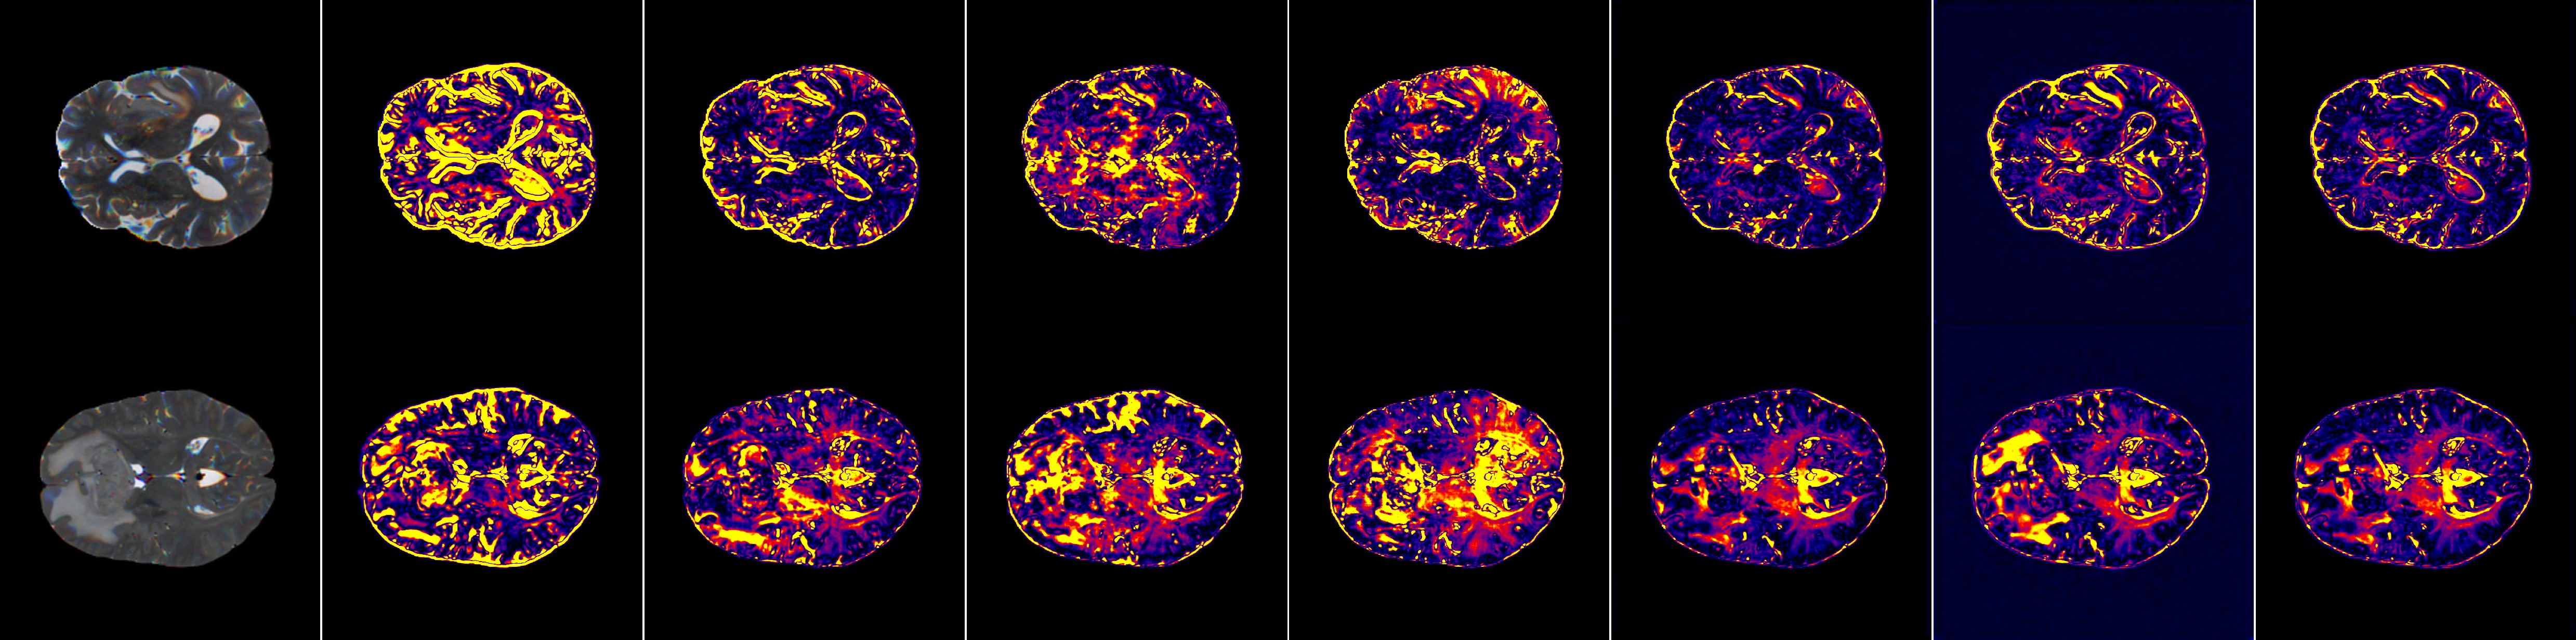

V-A Multi-Task Evaluation on BraTS 2023

On the BraTS 2023 [20] dataset, we conducted systematic comparative experiments between the proposed method and multiple existing models (Tables I,II,III). The experiments covered multi-task MRI translation (T1→T2, T1→FLAIR, T2→FLAIR), each of which has clear clinical relevance: the different sequences are widely used in practice, and their registration is stable with well-aligned structures, providing a fair basis for evaluating model performance. The comparative results are illustrated in the radar charts shown in Fig. 3.

For the T1→T2 task at a resolution of 256×256256\times 256, the proposed method achieved PSNR [35], SSIM [35], LPIPS [36], MS-SSIM [37], MSE [38], and NMSE [38] values of 26.9337 (vs. Pix2Pix [18]: 24.5867, ResViT [24]: 25.5658), 0.9137 (0.8642, 0.8966), 0.0850 (0.0722, 0.0679), 0.9342 (0.9008, 0.9114), 146.4111 (235.5794, 191.5842), and 0.0784 (0.1272, 0.1031), respectively.

At a lower resolution of 128×128128\times 128, the model maintained its advantages, achieving a PSNR [35] of 28.3101 (vs. BBDM [30]: 26.9471), SSIM [35] of 0.9281 (0.6921), and reductions in MSE [38] and NMSE [38] to 106.4440 (143.7848) and 0.0605 (0.0788).

For the T1→FLAIR translation task, at a resolution of 256×256256\times 256, the proposed method achieved PSNR [35], SSIM [35], LPIPS [36], MS-SSIM [37], MSE [38], and NMSE [38] values of 25.0454 (vs. Pix2Pix [18]: 23.1012, ResViT [24]: 23.8966), 0.8892 (0.8405, 0.8776), 0.0765 (0.0825, 0.0742), 0.9166 (0.8758, 0.8924), 224.6698 (344.4815, 290.7930), and 0.0635 (0.0928, 0.0820), respectively.

When evaluated at a lower resolution of 128×128128\times 128, the model continued to outperform alternative approaches, achieving a PSNR [35] of 25.9002 (vs. BBDM [30]: 24.9498), SSIM [35] of 0.9130 (0.8008), and reductions in MSE [38] and NMSE [38] to 190.5451(229.6841) and 0.0562(0.0647)

For the T2→FLAIR translation task, at a resolution of 256×256256\times 256, the proposed method achieved PSNR [35], SSIM [35], LPIPS [36], MS-SSIM [37], MSE [38], and NMSE [38] values of 26.2695 (vs. Pix2Pix [18]: 24.4305, ResViT [24]: 25.0538), 0.9116 (0.8712, 0.8954), 0.0782 (0.0693, 0.0591), 0.9396 (0.9132, 0.9231), 187.3451 (262.3100, 228.9338), and 0.0521 (0.0736, 0.0642), respectively.

At a lower resolution of 128×128128\times 128, the model maintained its advantage, achieving a PSNR [35] of 27.4374 (vs. BBDM [30]: 25.8915), SSIM [35] of 0.9419 (0.7994), and reductions in MSE [38] and NMSE [38] to 140.7312 (202.4337) and 0.0415 (0.0597), respectively.

Overall, the experimental results on the BraTS 2023 [20] dataset demonstrate the consistent superiority of the proposed method across all evaluated MRI translation tasks and resolutions. For each task—T1→T2, T1→FLAIR, and T2→FLAIR—the method achieved higher PSNR [35] and SSIM [35] values while reducing LPIPS [36], MSE [38], and NMSE [38] compared to baseline models, indicating improved image quality, structural fidelity, and pixel-level accuracy. Notably, the advantages were preserved even at a lower resolution of 128×128128\times 128, highlighting the robustness of the proposed approach in generating high-quality, structurally consistent images under reduced spatial resolution conditions. These findings collectively confirm the effectiveness and generalizability of our method in multi-task MRI translation scenarios.

V-B Cross-Dataset Generalization on IXI

The cross-dataset generalization performance of the proposed method was evaluated on the IXI [21] dataset for the PD→T2 translation task (Table IV). At a resolution of 256×256256\times 256, our model achieved a PSNR [35] of 33.0674, SSIM [35] of 0.9317, LPIPS [36] of 0.0422, MS-SSIM [37] of 0.9746, MSE [38] of 35.0427, and NMSE [38] of 0.0151, demonstrating substantial improvements in image quality, structural fidelity, and pixel-level accuracy compared to competing methods. Even at a lower resolution of 128×128128\times 128, the proposed method maintained its superiority, with PSNR [35] of 35.0093, SSIM [35] of 0.9655, LPIPS [36] of 0.0092, MS-SSIM [37] of 0.9910, MSE [38] of 23.3580, and NMSE [38] of 0.0109.

These results underscore not only the robustness but also the remarkable cross-dataset generalization capability of our proposed approach in MRI translation tasks. The model consistently maintains high image quality, structural fidelity, and pixel-level accuracy across different resolutions and diverse data distributions, demonstrating its adaptability to varying acquisition conditions and scanning protocols. Such strong generalization suggests that our method can be reliably applied to heterogeneous clinical datasets, facilitating broader practical deployment and potentially enhancing the performance of downstream diagnostic or analytic tasks that rely on accurate multi-modal MRI synthesis.

V-C Zero-Shot Transfer on BraTS 2019

To evaluate the generalization capability of the proposed method on the same-modality MRI tasks, we conducted zero-shot testing on the BraTS 2019 [22] dataset, directly applying the model trained on BraTS 2023 [20] (Table V).

At a resolution of 256×256256\times 256, our method achieved PSNR [35], SSIM [35], and NMSE [38] values of 23.4793 (vs. Pix2Pix [18]: 21.8851, ResViT [24]: 22.5174), 0.8911 (0.8341, 0.8708), and 0.1216 (0.1712, 0.1464), respectively, significantly outperforming existing approaches. These results indicate that the model can maintain strong structural fidelity and low error on previously unseen datasets.

At a lower resolution of 128×128128\times 128, the proposed method similarly demonstrated superior performance, achieving PSNR [35], SSIM [35], and NMSE [38] of 24.0789 (vs. BBDM [30]: 23.0870), 0.8949 (0.6622), and 0.1127 (0.1360), respectively. Notably, although BBDM [30] achieved a comparable PSNR [35], its SSIM [35] was only 0.6622, substantially lower than our method (0.8949), indicating a deficiency in structural preservation. In addition, our method also achieved higher MS-SSIM [37] (0.9137 vs. 0.8921), confirming its robustness and effectiveness under zero-shot cross-dataset conditions.

Refer to caption

Figure 3: Radar charts comparing the performance of multiple models on various MRI image translation tasks across five datasets. Each chart shows seven different models evaluated on multiple metrics (PSNR, SSIM, LPIPS, MS-SSIM , MSE , NMSE). The top row presents three charts corresponding to the BraTS 2023 dataset for T1→T2, T1→FLAIR, and T2→FLAIR tasks. The bottom row shows two charts for the IXI dataset (PD→T2) and the BraTS 2019 zero-shot generalization task. Metrics are normalized for visualization to facilitate a clear comparison of each model’s strengths and differences.